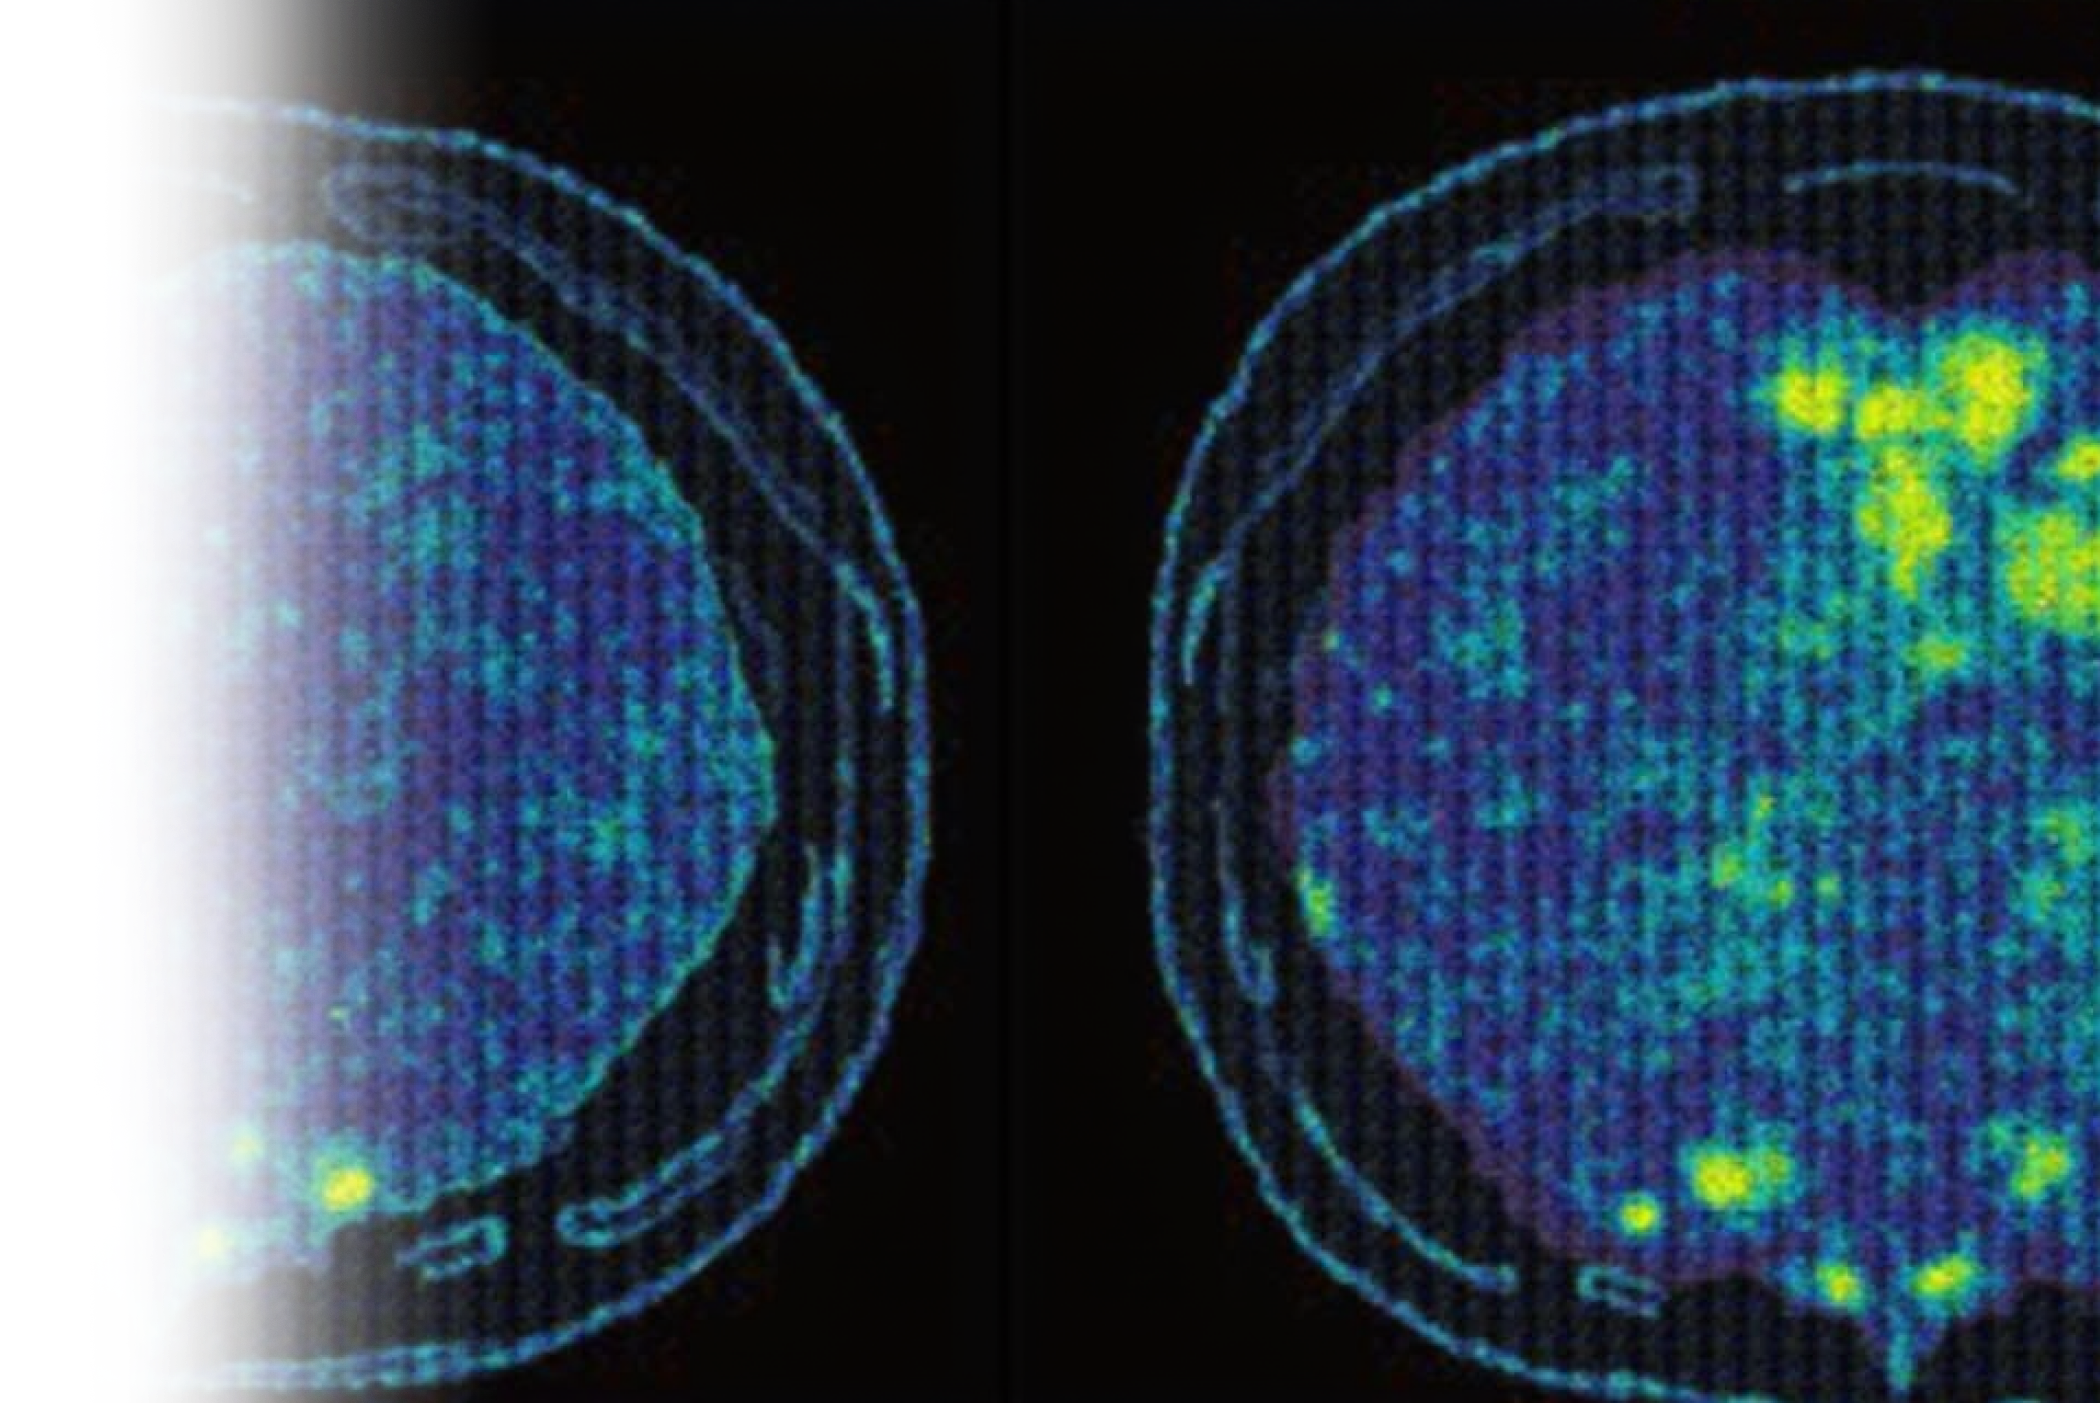

Компьютерная томография мягких тканей с контрастированием – важный метод исследования состояния мягких тканей с внутривенным ведением йодсодержащего контрастного препарата.

КТ мягких тканей с контрастированием является более информативным методом диагностики, в сравнении с нативным (без введения контраста) исследованием ввиду большей контрастности тканей, что позволяет более точно определить состояние мягких тканей и выявить патологии.

Пациенту внутривенно вводится контрастное вещество, которое обеспечивает более качественную видимость органов на получаемых снимках, что позволяет выявить даже самые незначительные изменения в исследуемой области.